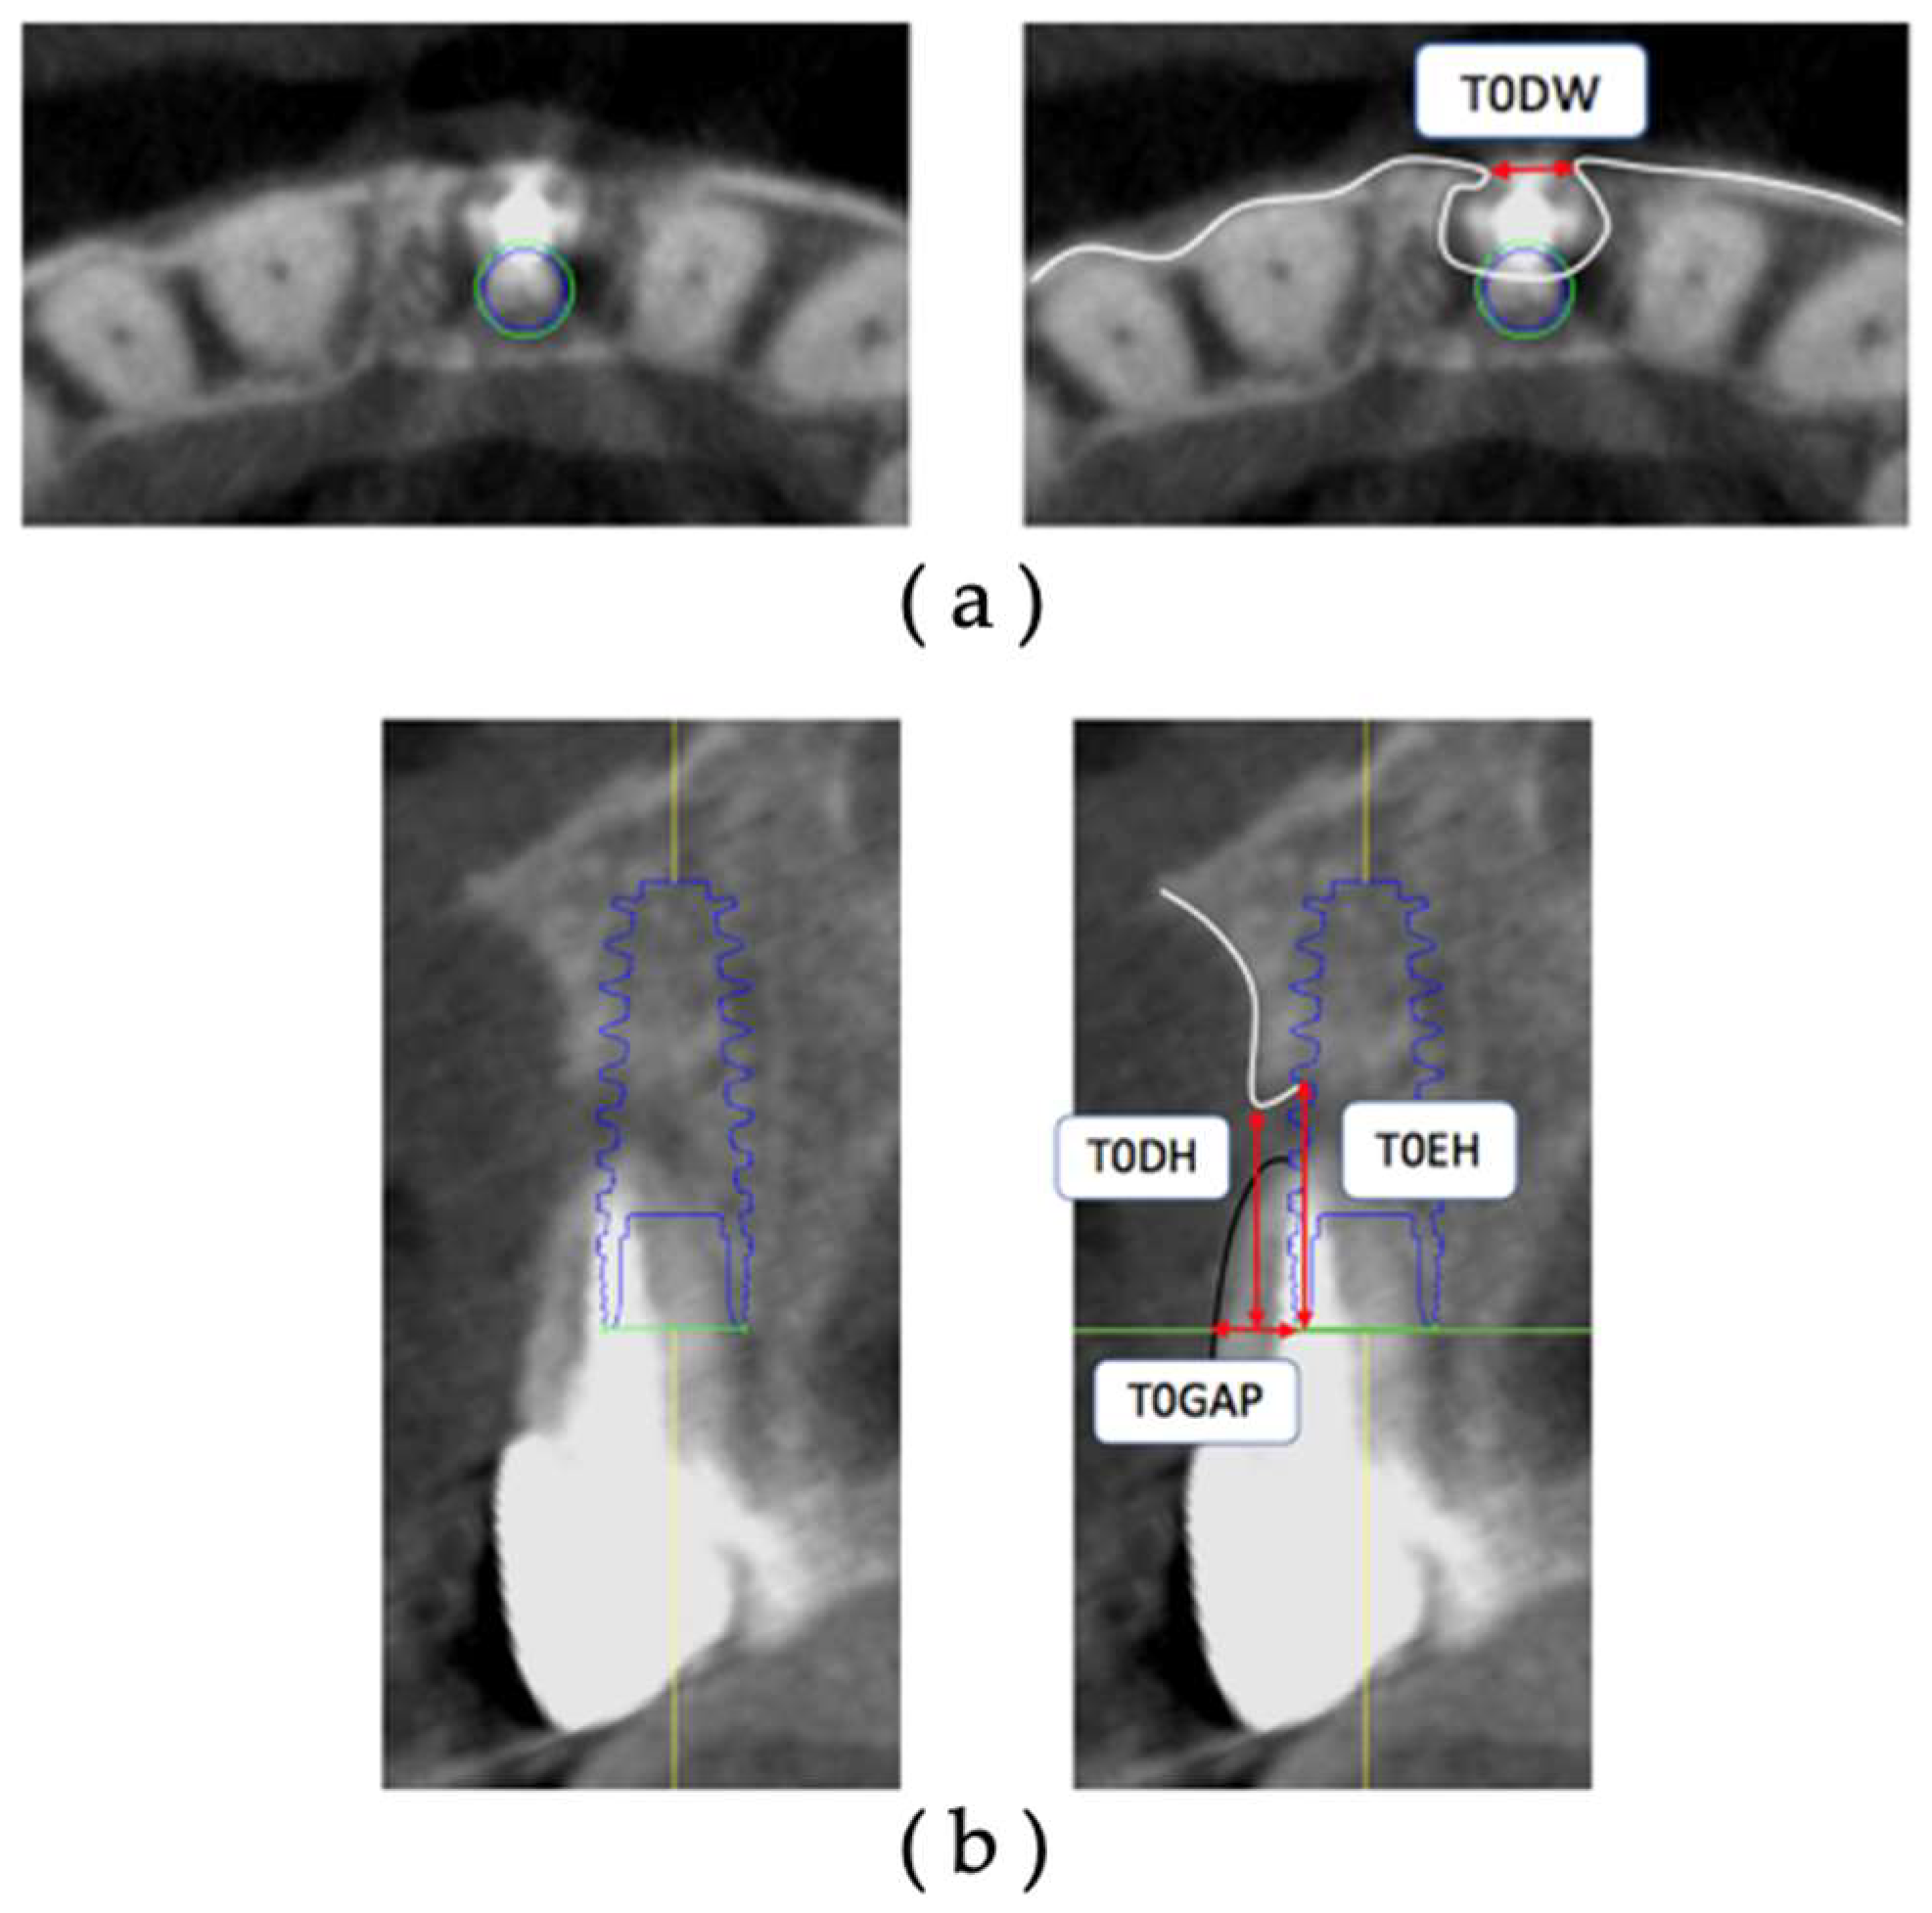

The CBCT data of T0 was extracted, and the facial alveolar bone morphology before extraction was measured on the diagnostic imaging software (Figure 3). All measurements were made using axial- and cross-sections acquired with the IM as the reference.

The measurement sites were measured on the obtained axial section with respect to the platform level. The measurement sites were the facial alveolar bone dehiscence width (T0DW) on the acquired axial section and the facial alveolar bone dehiscence height (T0DH), the amount of exposure height (T0EH) of the implant body, and the gap width of the tooth root (T0Gap) starting from the most labial side of the IM on the cross-sectional section. All measurements are in millimeters.

Figure 3. Measurement items for preoperative facial alveolar bone morphology. (a) Axial section. T0DW, mesial and distal width of dehiscence of the facial alveolar bone. (b) Cross-sectional section. T0DH, depth of dehiscence of the facial alveolar bone; T0EH, amount of implant exposure; T0GAP, buccolingual width of the tooth root based on the most facial side of the IM.